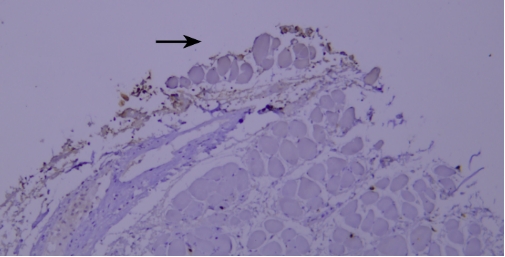

典型实例:人前列腺石蜡组织切片TIMP-1染色,因干片出现假阴性(黑色箭头区域)。

解决建议:使用加入Tween-20的缓冲液,可有效防止切片干燥。